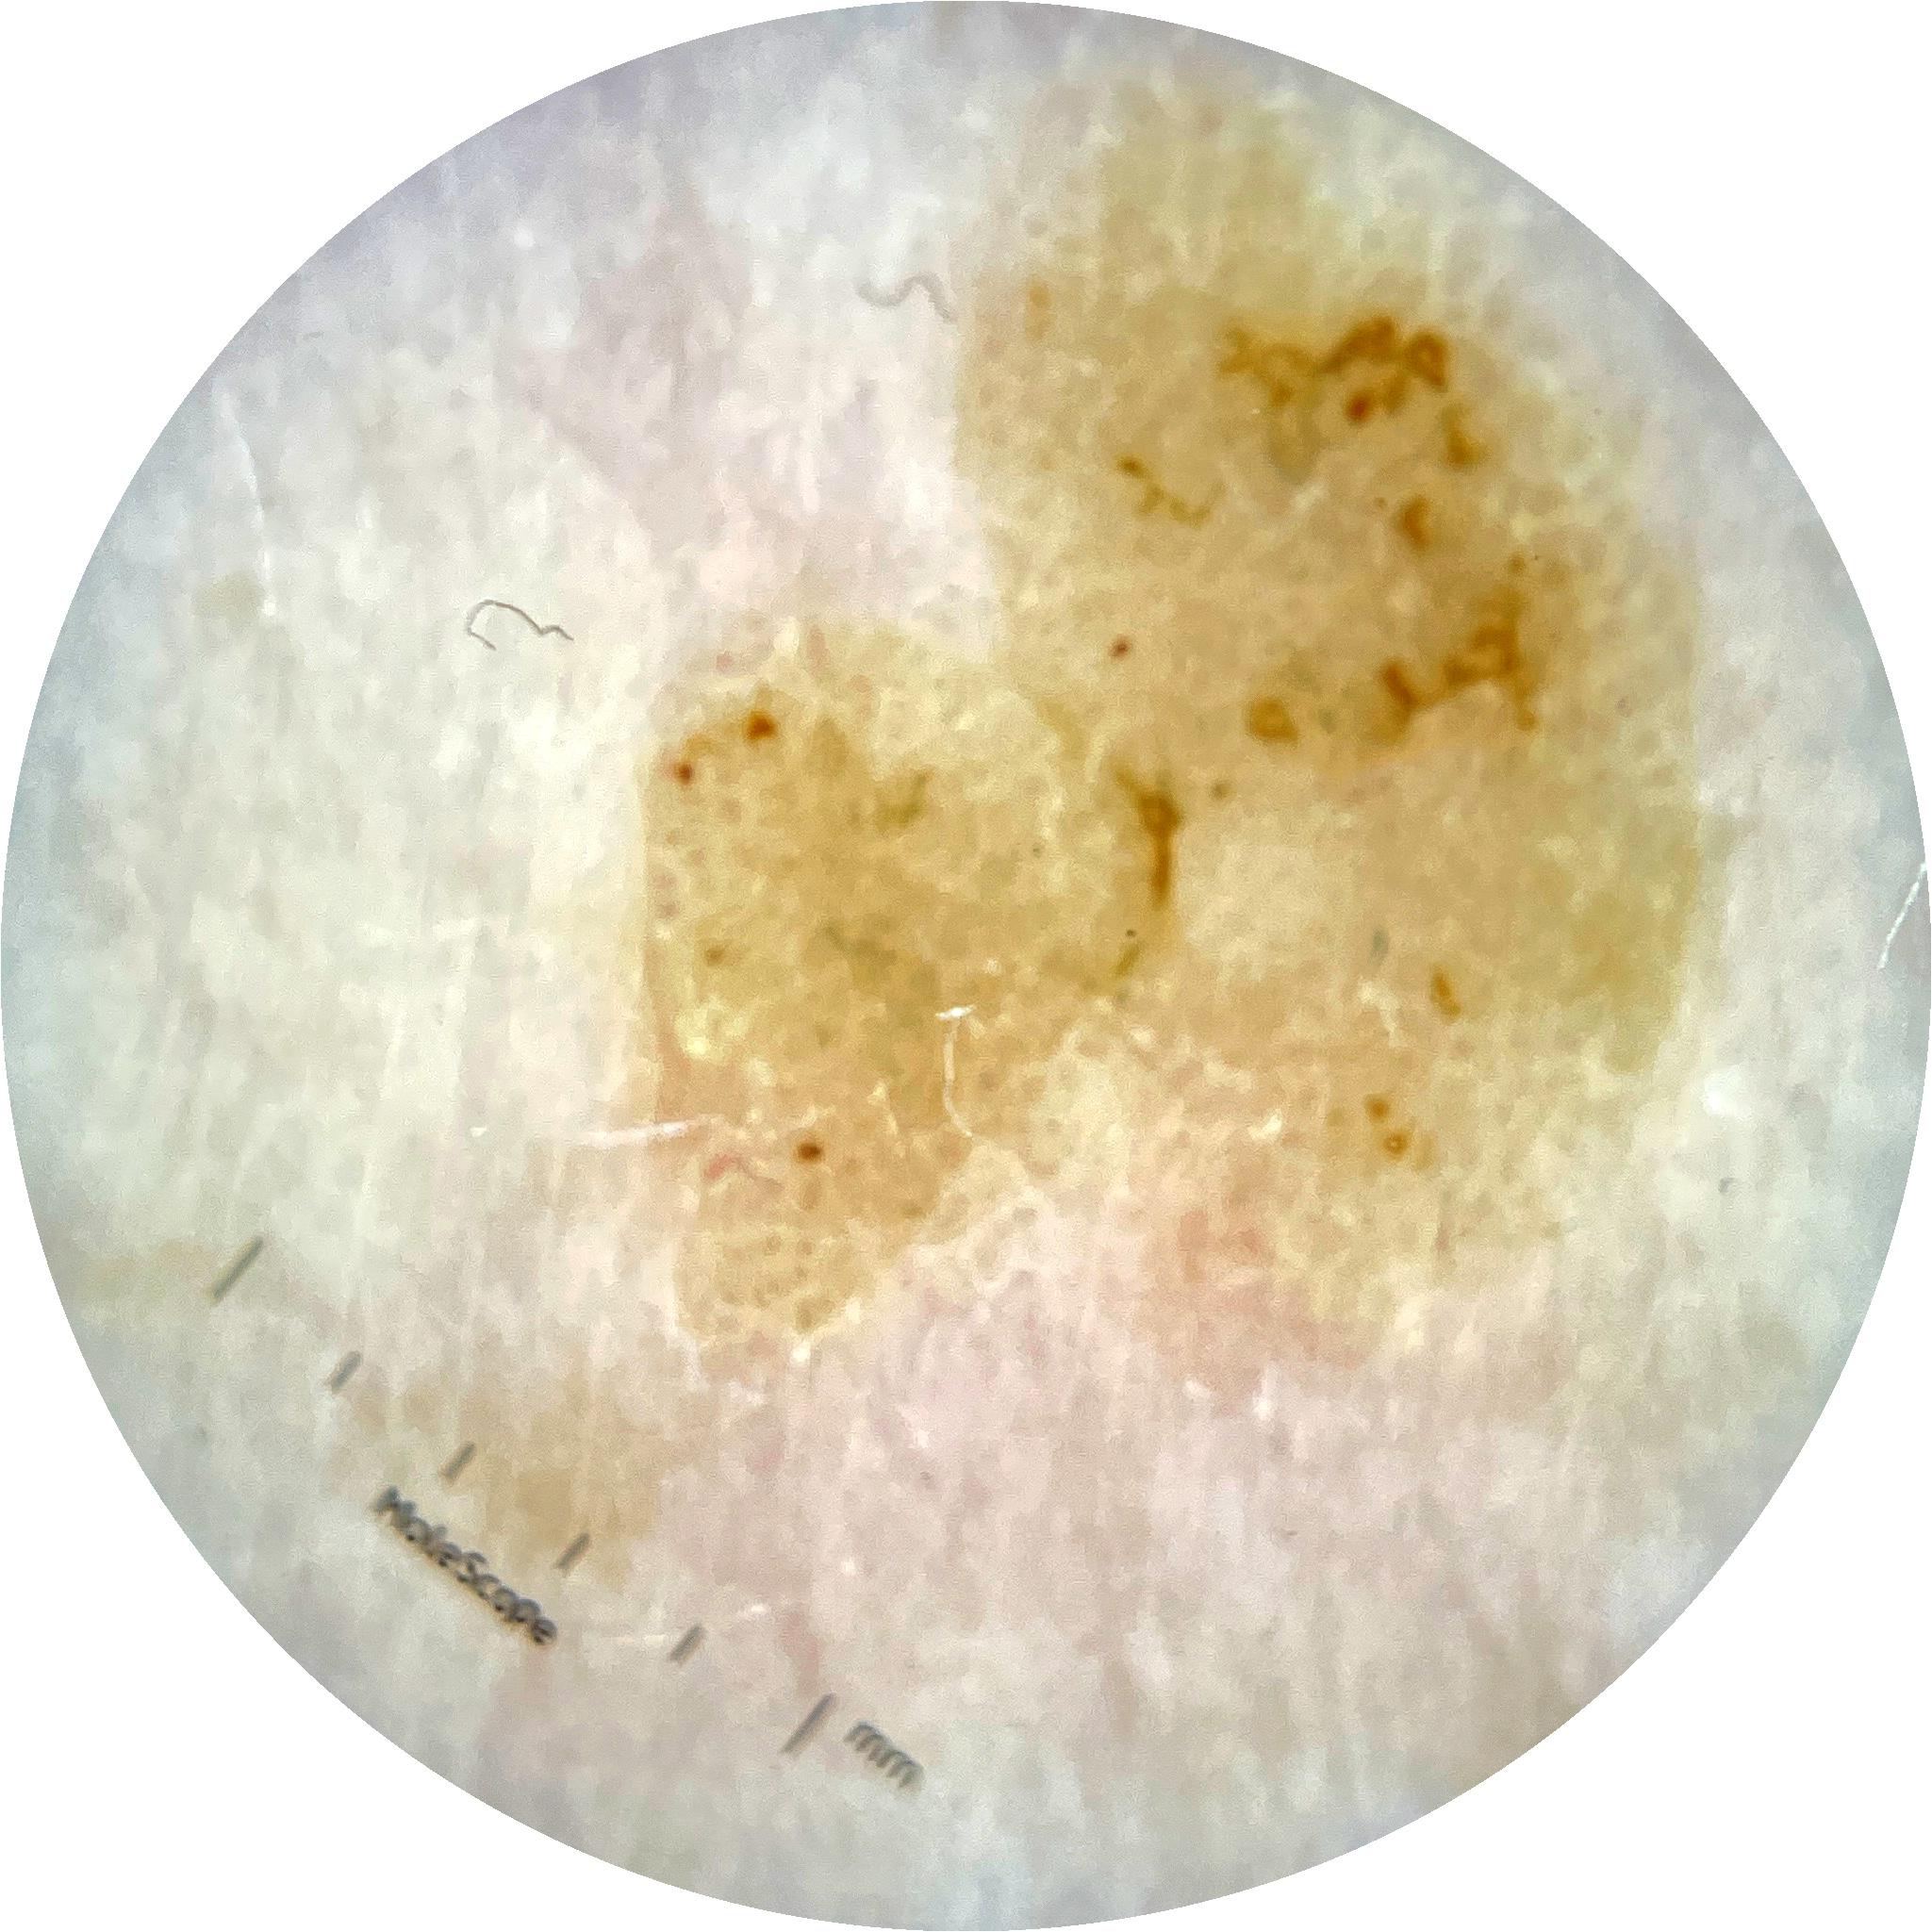

ISIC_9785574

Field Value

acquisition_day 148

age_approx 45

anatom_site_1 Head and neck

anatom_site_general head/neck

diagnosis_1 Benign

diagnosis_confirm_type single image expert consensus

image_type dermoscopic